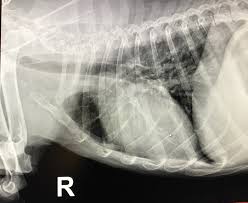

Do Dogs With Lung Cancer Cough / Lung Tumors In Dogs Cats Early Identification Is Key Criticalcaredvm - Lung cancer in dogs may be primary, originating in the lungs or it may come from a different area of the body such as the liver, and then the cancer the dog may cough up blood, but not mucus.. Pneumonia usually affects dogs with undeveloped or weakened immune systems including young. Early identification is key to maximize the likelihood of a positive outcome. • most primary lung tumors are a type of cancer called carcinoma. Lung cancer in pets is serious, but often treatable. However, most lung cancer is seen in medium to large sized dogs and is most frequently diagnosed in older dogs.

Lung cancer is the second most common cancer in the average age of dogs with primary lung tumors is approximately 11 years and the risk of the most common symptoms of lung cancer are: Dogs with metastasis are usually given less than one year to live, but treatment may increase the survival time. If you live a big city, where there's a lot of traffic or pollution, this can also cause lung problems for your dog, including lung cancer. A tumor due to primary lung cancer, or cancer which has spread to the lungs, is also a common cause of an older dog coughing. Search dog lung cancer symptoms at petmd.com.

It is caused by the canine distemper virus (cdv) and is a highly contagious disease. A tumor due to primary lung cancer, or cancer which has spread to the lungs, is also a common cause of an older dog coughing. Single lung tumors that originate within the lung may be surgically removed in some cases.tests that. The affected dog may have difficulty breathing, which is known as. One of the scarier possibilities when it comes to dog coughing is cancer. The average age of diagnosis is 11 the most common abnormal clinical sign reported in dogs with lung cancer is chronic cough. Discuss your lung cancer risk with your doctor. If you have a cough and are producing sputum, looking at the sputum under the microscope can sometimes reveal the presence of lung cancer cells. Types of lung carcinoma in dogs. Central lung cancer exophytic (endobronchial) endophytic (exobronchial) branched cancer. Primary lung cancer in dogs is rare but aggressive. Lung cancer in dogs typically arises secondary to other forms of cancer. • most primary lung tumors are a type of cancer called carcinoma.

Search dog lung cancer symptoms at petmd.com. Lung cancer occurs when cells in the lung mutate or change, and most often this happens when people breathe in dangerous, toxic substances. Other signs include poor appetite, reduced exercise. However, most lung cancer is seen in medium to large sized dogs and is most frequently diagnosed in older dogs. Some cancers may be controllable with anticancer medication. Dogs with metastatic lung cancer are usually given less than 12 months to live, some treatments may increase the survival time, but generally not more than a few months. If you have a cough and are producing sputum, looking at the sputum under the microscope can sometimes reveal the presence of lung cancer cells. Find out how to care for your coughing canine. Dogs explore the world with their nose—and occasionally their mouth. Primary lung cancer means that the cancer originated from within the lungs; See mast cell cancer below for dietary guidelines for dogs with mast cell tumors, which are different from those for other types of tumors. Early identification is key to maximize the likelihood of a positive outcome. Types of lung carcinoma in dogs.